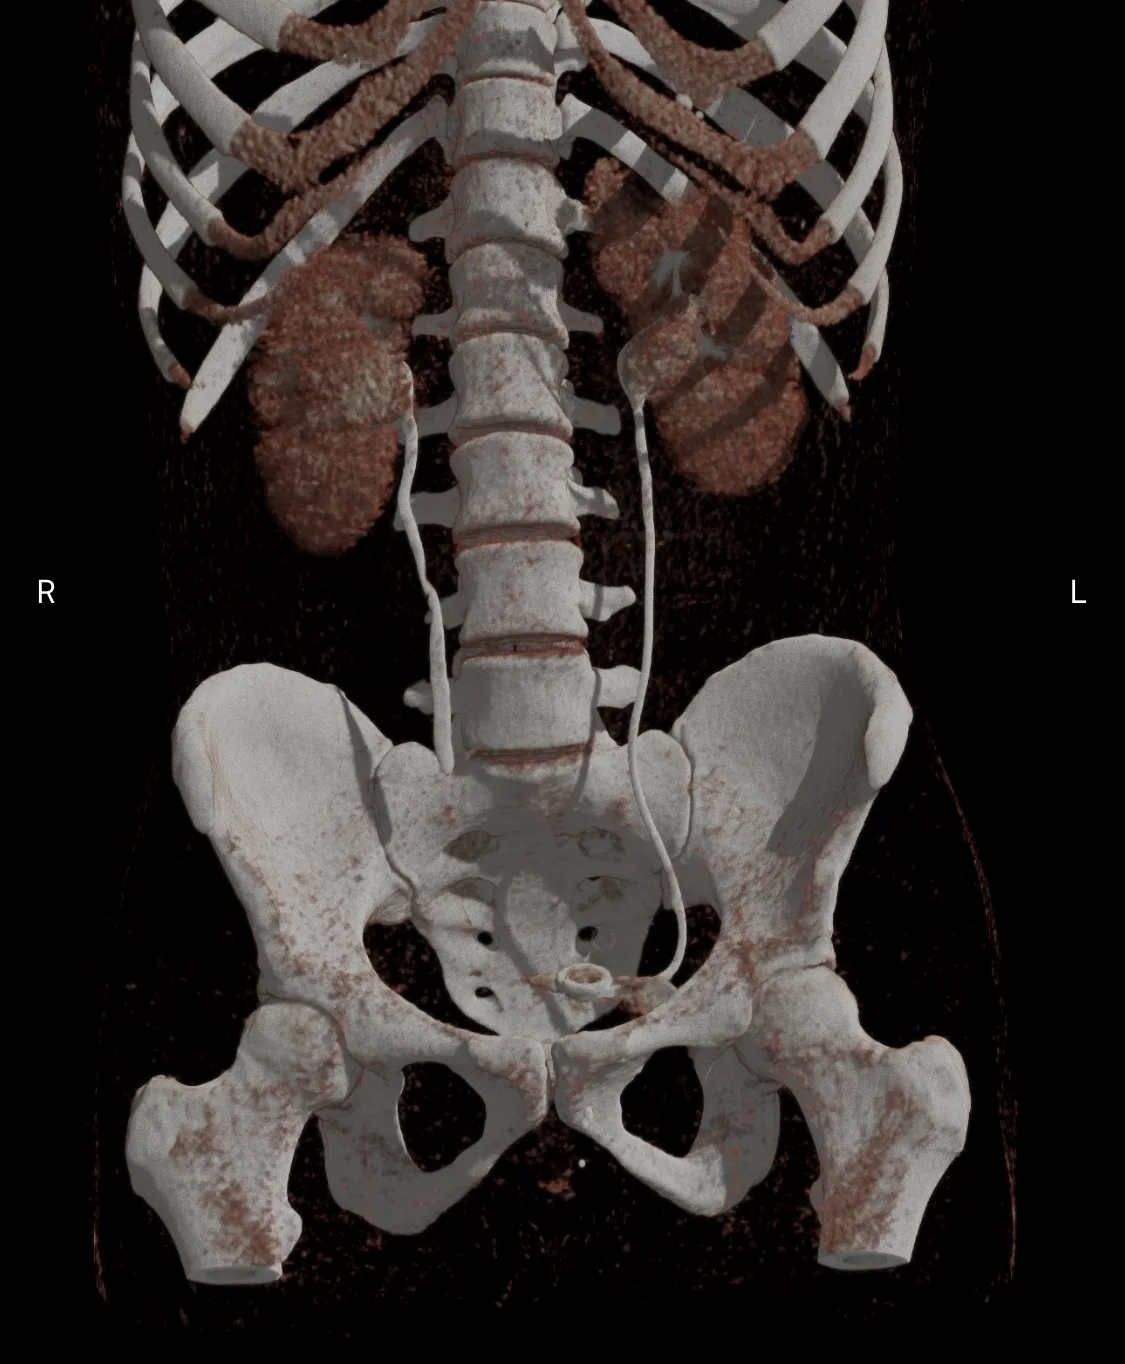

Вот такие плечики у пациента 29 лет! Во время эпидемии COVIDa-19 перенёс тяжёлую форму, лечили, в том числе, высокими дозами кортикостероидов, так что остеонекроз, который мы имеем возможность видеть в головках плечевых костей, по всей видимости, развился, как осложнение этого вида терапии. Хотя, при этой инфекции возникает ещё и гиперкоагуляция, которая и сама по себе является фактором риска развития некроза костей. В литературе такие случаи описаны и известны, есть описания развития остеонекроза даже четырёх костей одновременно (головок бедренных и плечевых костей), причём, развился он аж через полгода после окончания терапии. В нашем случае справа некроз привед к фрагментации головки плеча. Понятное дело, что функции плечевых суставов нарушены, в том числе, за счёт развития грубого вторичного артроза. Видимо, тотальная артропластика потребуется...